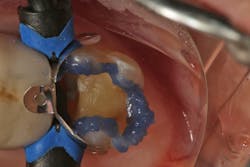

The quadrant is isolated using the Isolite system. An anatomically designed sectional matrix system is placed to ensure proper contact and contour of the final restoration.

Because of the extent and depth of the preparation, it was decided to use a selective-etch technique (figure 7). This technique will place phosphoric etch only on the enamel of the preparation with care taken to minimize contact of the etchant on the dentin. The thought process here is that with such deep dentin exposed, it is wise not to irritate the pulp with the acid-etch. This technique is made possible with the use of a universal bonding agent (Futurabond U, Voco) by taking advantage of its self-etching properties. The etch is rinsed after 20–30 seconds, and then the universal bonding agent is applied and light-cured.

The restorative composite (GrandioSO, Voco) is placed in two separate increments. Each increment is light-cured for 20–30 seconds. An anatomically designed diamond bur (Occlusinator, Strauss) is used to create the initial anatomic form and occlusion. This is then polished to a high shine using a series of composite polishers (Dimanto, Voco).